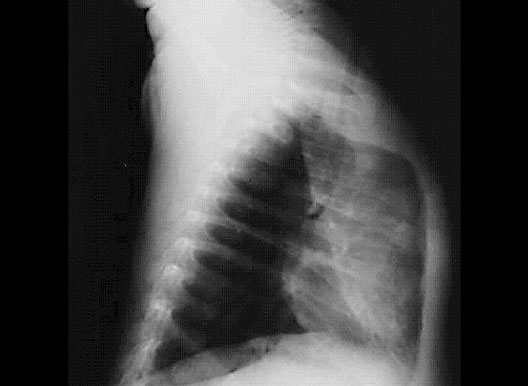

Lateral Chest X-Ray

1. Diaphragm

2. Sternum

3. Heart

4. Lung